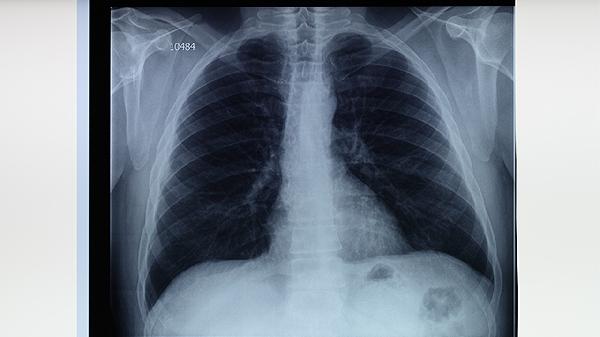

睡眠剝奪會導致皮質(zhì)醇晝夜分泌紊亂,持續(xù)高水平糖皮質(zhì)激素可能抑制T細胞增殖。褪黑素分泌減少可能削弱抗氧化防御系統(tǒng),增加肺部組織對結(jié)核桿菌的易感性。這種情況可能需進行胸部CT檢查,排除肺門淋巴結(jié)腫大等病變。

保持每天7-8小時高質(zhì)量睡眠有助于維持免疫穩(wěn)態(tài),夜間工作人群應保證白天睡眠環(huán)境黑暗安靜。飲食注意補充優(yōu)質(zhì)蛋白和維生素A/C/D,適量食用牛奶、雞蛋、西藍花等食物。出現(xiàn)持續(xù)咳嗽超過2周、午后低熱、痰中帶血等癥狀時,應及時到結(jié)核病防治機構(gòu)進行痰涂片檢查和胸部影像學評估。確診患者需嚴格遵醫(yī)囑完成6-9個月規(guī)范抗結(jié)核治療,常用藥物包括異煙肼片、利福平膠囊、吡嗪酰胺片等,治療期間須定期監(jiān)測肝功能。